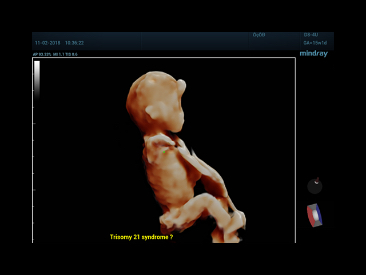

Since the company was founded, Mindray is continuously exploring new ways to improve diagnostic confidence. Powered by the most revolutionary ZONE Sonography? Technology, the ZST+ platform brings ultrasound image quality to a higher level by zone acquisition and channel data processing.

Thanks to the innovative, software-driven ZST+ platform, the Resona series is continuously evolving with the leading-edge technologies to meet the most challenging diagnostic demands in womenŌĆÖs health practice. More importantly, it is designed with the understanding that the wisdom of experts is always precious, and you need more intelligent partner for enhanced speed and confidence. Finally, Resona series with Zone Intelligence provides a total solution to help you with diagnostic confidence, efficiency, and standardization across different diagnostic challenges in todayŌĆÖs demanding and overburden hospital environment.